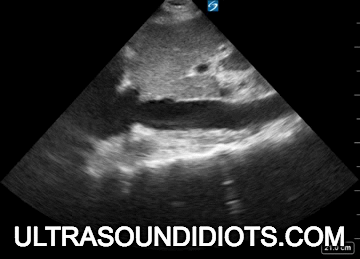

Echo Subcostal Exams